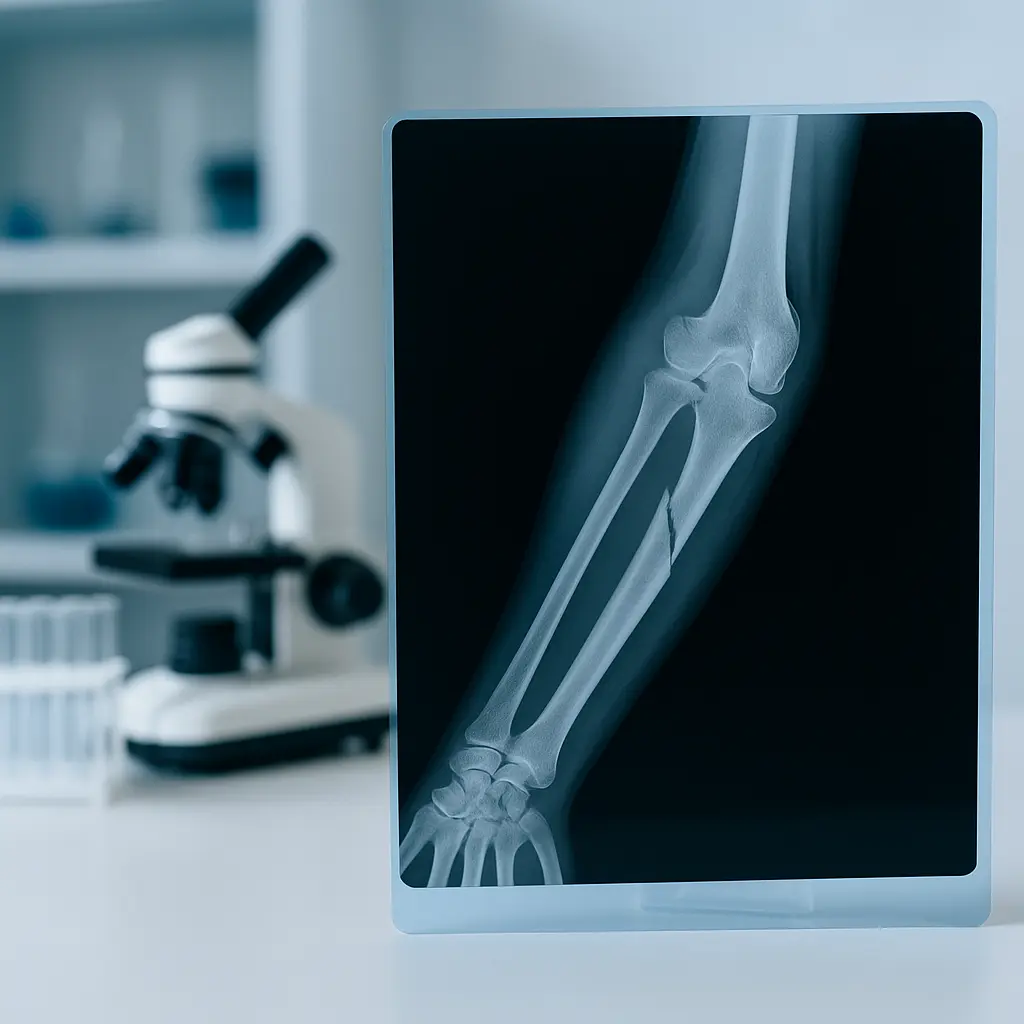

A broken arm occurs when one or more of the three major arm bones—the humerus (upper arm), radius, or ulna (forearm)—crack or break due to sudden impact or strain. These injuries often result from car crashes, sports accidents, or falls. Early diagnosis and treatment are key to preventing long-term complications.

Arm fractures vary in severity, from hairline cracks to compound breaks that pierce the skin or affect nearby tissues.

Radius and Ulna Fractures (Forearm)

Common in vehicle accidents or sports, these fractures may occur together and impact grip strength or wrist stability.